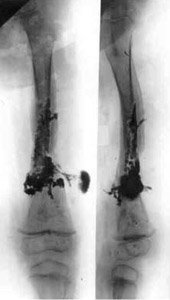

Results of treatment.